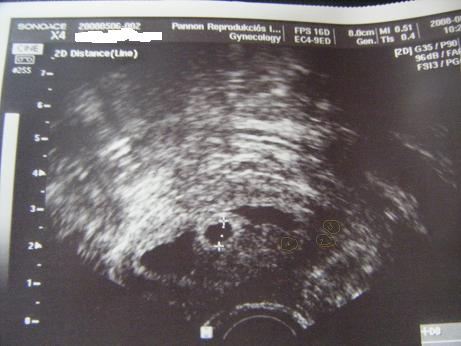

Jól emlékszel, én is használtam felváltva Clostit és Merionalt. 3. naptól napi egy Closti, 9. és 11. napon 1-1 Merional, és ebből a koktélból lettek a Tojáskáim